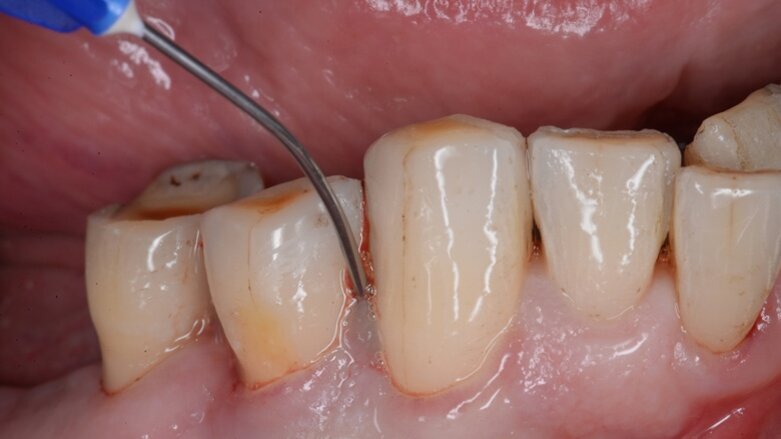

Inwiefern hängt der Erfolg einer regenerativen Therapie von den verwendeten Materialien ab? Der Erfolg der regenerativen Maßnahme hängt in erster Linie von der Einbettung in ein erfolgreiches parodontales Gesamtkonzept ab. Dies beginnt mit der antiinfektiösen Therapie, läuft weiter in einer sauber durchgeführten regenerativen Maßnahme und endet in einer guten postoperativen und langfristigen Nachsorge. Die Verwendung verschiedener Materialien bedingt nicht in erster Linie den Erfolg, sondern ermöglicht es, die Eingriffe weniger invasiv und effizienter zu machen.

Welchen Einfluss hat das bakterielle Gleichgewicht im Mund auf die Behandlung? Einen großen Einfluss. Sowohl die antiinfektiöse Therapie, um das bakterielle Gleichgewicht nachhaltig zum Positiven zu verändern, die direkt präoperativ durchgeführt antimikrobielle Behandlung, um die Bakterienzahl vor dem parodontalen Eingriff zu minimieren, als auch die postoperative Infektionskontrolle haben einen deutlich positiven Effekt auf das Ergebnis der Regeneration.